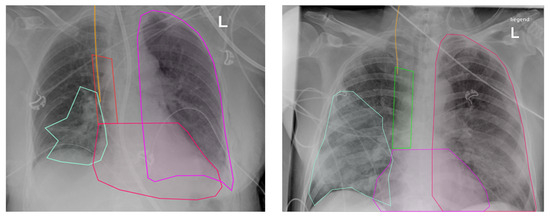

2.2. Segmentation Process

- Anatomical Structures: These were categorized based on their level of difficulty in terms of identification and annotation. The structures included were the left lung (easy), the heart (medium), and the superior vena cava (VCS) (hard).

- Foreign Material: The CVC, if present, was annotated. In many cases, the CVC had to be distinguished from other tube-like foreign material, e.g., dialysis catheters. Twelve of the images showed a misplaced CVC.

- Pulmonary Pathology: Pneumonic opacity was annotated. All participants were aware that all patients in the cohort were treated for pneumonia.